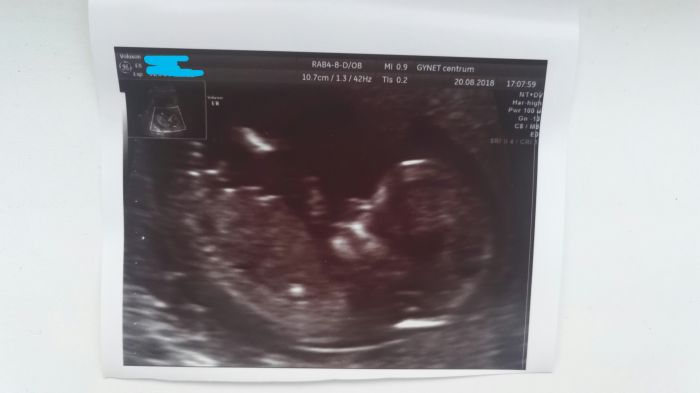

Holky ja jsem dneska nervooznii :-( 15:10 jdu ke kozni (mam vystouple znamenko na prsnim dvorci a do budoucna chci kojit tak musi jit pryc ) ...no a 17:30 jdeme na prvni screening

Holky tak vse super

Miminko je v poradku meri 7 cm bez noh protoze ty mel v tureckem lehu

Srdicko tluce jak ma mame dve ruce hihi no kraasna nosanek ma asi po me :-D a na 100% to je kluk jako buk